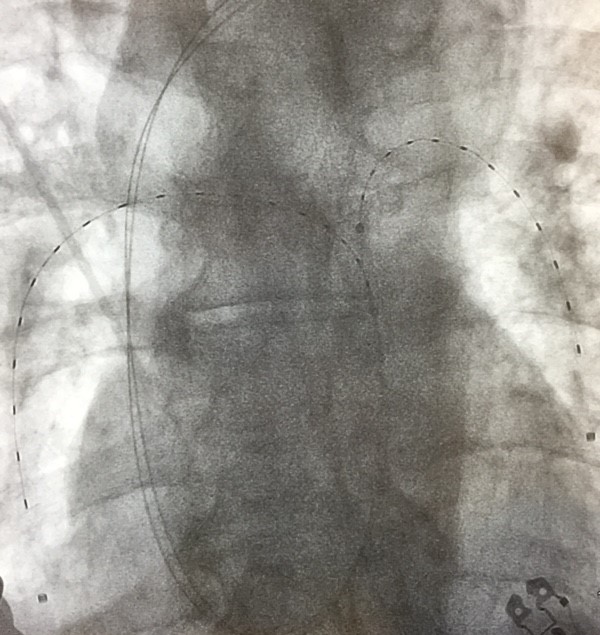

Two EKOS catheters are in place, one in each lung, during the treatment of a PE. Images courtesy of Timothy Smith, MD.